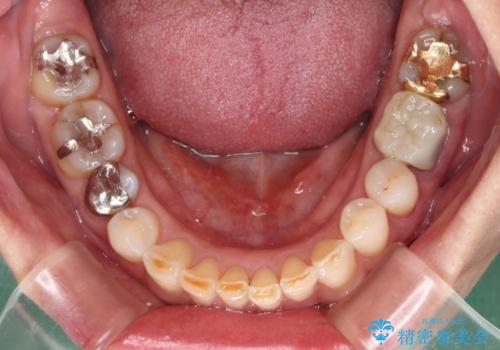

- 奥歯が咬めないくらいに痛いとのことで来院された患者様です。

痛みの強い歯は、歯髄組織が強い炎症を起こしており、神経を取り除く必要であったため、速やかに根管治療を行いました。

その後、オールセラミッククラウンにて補綴治療を行う予定でしたが、処置した歯以外にも治療が必要と思われる歯があったり、デコボコした歯列も気になるとのことで、患者様希望によりインビザラインにてマウスピース矯正を行うこととしました。

まずは矯正治療前に必要なむし歯処置を行い、その後矯正治療を行ってから、最後にオールセラミッククラウンなどで補綴治療を行うこととしました。

咬合力が非常に強く、全体的に歯が擦り減っている状態であったので、理想的な咬み合わせを達成することは難しく、また咬合力が強い方のマウスピース矯正は、思い通りに動かないことがあるため、ワイヤー矯正の方が望ましいように思えました。